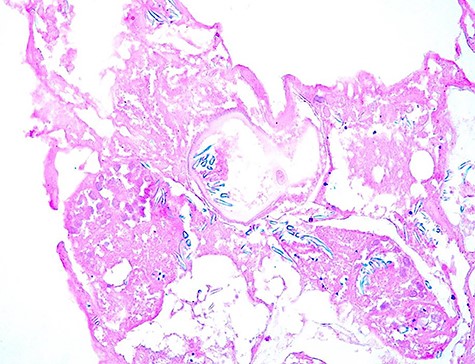

Anatomo-pathological examination revealed presence of a multilocular renal cystic lesion containing many hyaline acellular membranes. The cystic layer was made of a fibrotic tissue contain many inflammatory cells with cholesterol clefts (Figs 3 and 4).

Pathological examination revealed presence of a laminated; acellular and eosinophilic membrane with presence of many scolexes in the cystic lumen. (HE; 100X).

The scolexes showed presence of many hooklets that appeared refractile at microscopic examination (HE; 400X).